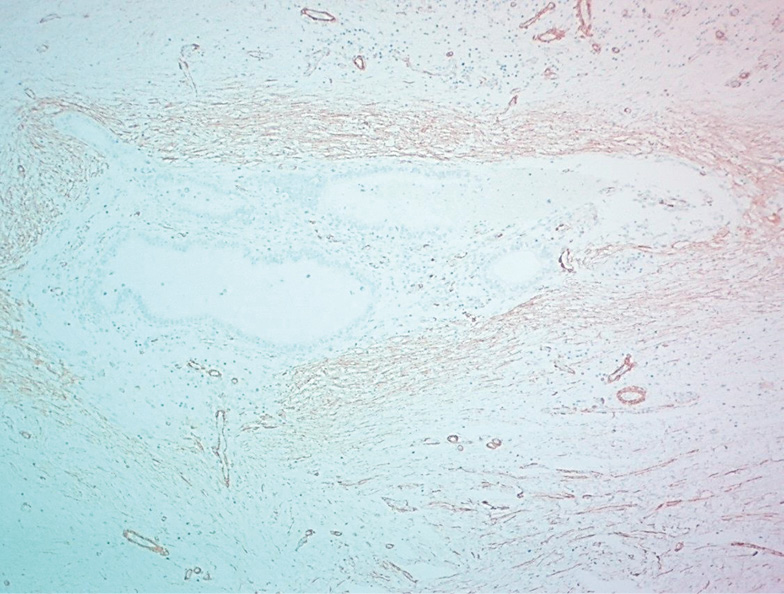

Macro- and microscopic studies revealed that the postoperative scar endometriosis foci formed nodules of different sizes without clear capsules. This aspect was due to the proliferation of connective tissue fields with numerous collagen fibers around and between heterotopias, detected in all cases (Fig. 6).

Fig. 6. Perifocal fibrosis with the collagen fibers proliferation. Painting with picrofuxin according to the Van Gieson method, zoom ×100

Рис. 6. Перифокальный фиброз с разрастанием коллагеновых волокон. Окраска пикрофуксином по методу Ван-Гизона, увеличение ×100